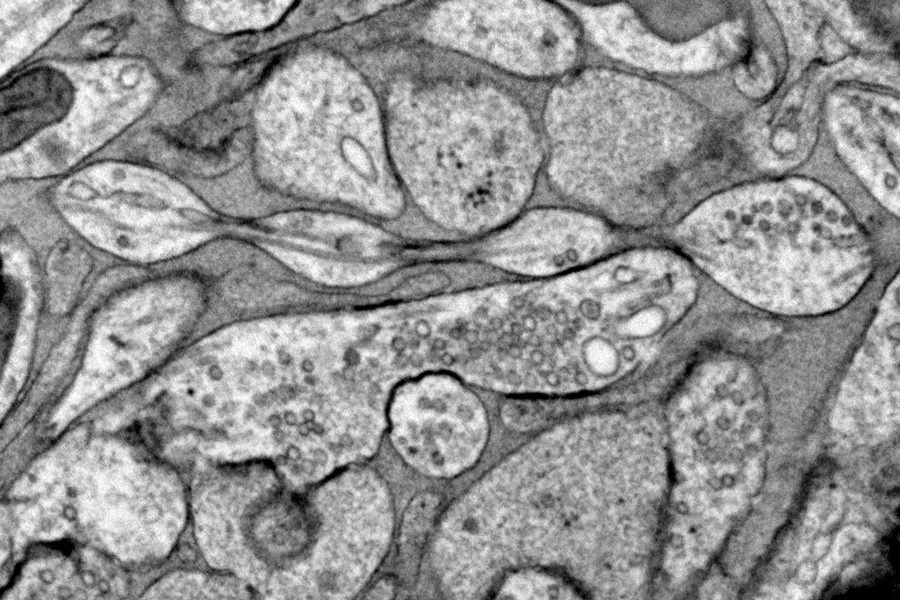

Используя электронный микроскоп, она заметила равномерно расположенные маленькие жемчужины диаметром около 200 нанометров вдоль аксонов мыши. Капли были меньше и более равномерно расположены, чем стрессовые шарики Летерье, и они ничего не содержали, что предполагает, что они не были результатом клеточных пробок.

Это открытие перекликается с другими: Ватанабе заметила похожие жемчужины аксонов у круглых червей в 2013 году, но не стала исследовать их дальше, а Буркхардт недавно увидела их у гребневиков. Грисволд также говорит, что видела жемчужины аксонов в мозговой ткани человека, обработанной методом заморозки под высоким давлением, хотя она и ее коллеги еще не опубликовали это открытие.